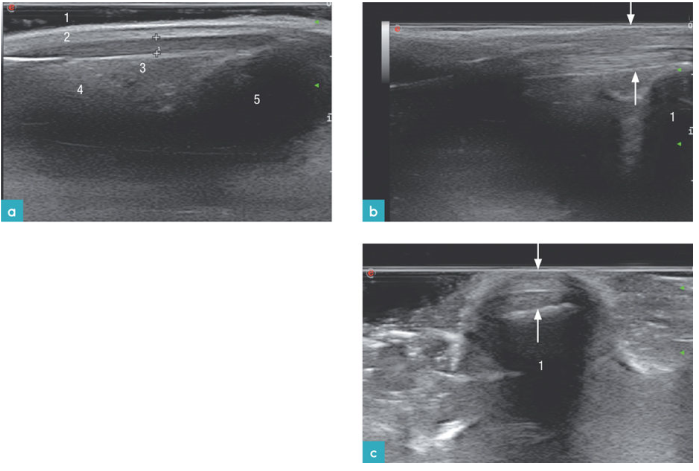

正常肌肉的长轴观与短轴观图像略有不同。长轴观肌纤维图像中可见低回声结构中穿插着小幅度倾斜的高回声线状结构;短轴观中则为低回声结构中出现均匀散在的高回声小圆点结构(图2)。肌肉或肌间筋膜在图像上表现为高回声细带状物。

将探头垂直于肌腱纤维放置时,可见肌腱为回声高于肌肉组织的,回声均一的线性结构(图3)。当探头声束不垂直于肌腱时,例如扫查肌腱的起止点时,肌腱则表现为低回声,注意不要将其判定为病变。肌腱周围可见一薄薄的低回声环状影像,是腱鞘和其中的少量液体。